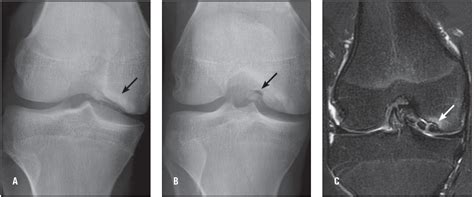

Afterwards, the fracture had healed, and 3 months postoperatively, there was a full range of motion. Hoffa fractures are caused by shear stress between the femoral condyle and tibial plateau.

Treatment of partial articular fracture, medial condyle. Contraindications to sw treatment (infection or cancer. Medial condyle fractures are intraarticular, extending into the elbow joint and require urgent open reduction internal fixation (orif). Posterior femoral line (white) c. Used for complex medial femoral condyle fractures. Femoral neck fractures in the elderly are frequent, represent a great health care problem, and have a significant impact on health insurance costs. Femoral neck fractures carol lin, md & brad merk, md original authors: This case report describes a periprosthetic fracture of the medial femoral condyle that occurred during an oukr. The distal end of the femur has medial and lateral condyles. Medial femoral condyle fracture kneeall software. In neglected hoffa fractures despite nonunion, there is a risk of missing we help you select the appropriate treatment of partial articular fracture, medial condyle, sagittal simple located in our module on distal femur. Implantation of bipolar prosthesis for treatment of medial femoral neck fractures in the elderly. For simple fractures of the medial condyle, a medial parapatellar surgical approach is most commonly used. Keywords femur á medial condyle fracture á nonunion á retrograde intramedullary nail. Treatment of distal femur fractures. .between medial and lateral vastus muscles causing impingement of the superolateral aspect of hoffa fat pad between the inferior patella and the lateral femoral condyle. Medial condyle extends more distal than lateral condyle.